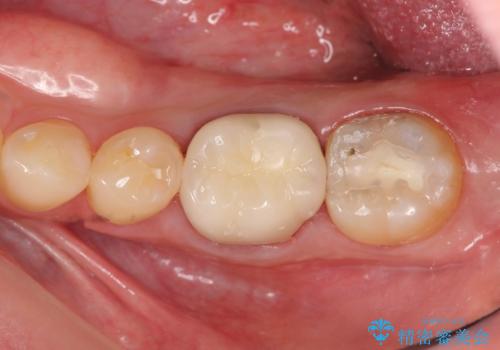

放置してしまった歯 根管治療からの機能回復

根管治療の途中で放置してしまっていた歯を、最終的に機能回復できるよう治療を行っていきます。

- 13万円(仮歯・ファイバーコア・ジルコニアクラウン)費用は治療当時の料金となります